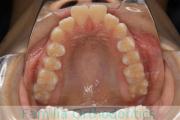

上の前歯の並びが気になるのできれいにしたい、ということで来院されました。マウスピース型矯正装置のひとつ、インビザライン/InvisalignR(薬機法および医薬品副作用被害救済制度の対象外)を用いて治療しました。

非抜歯で2年弱、20回程度の通院で治療が完了しました。

マウスピース矯正は、患者さんの協力に治療結果が左右されるところはリスクと言えるかもしれません。